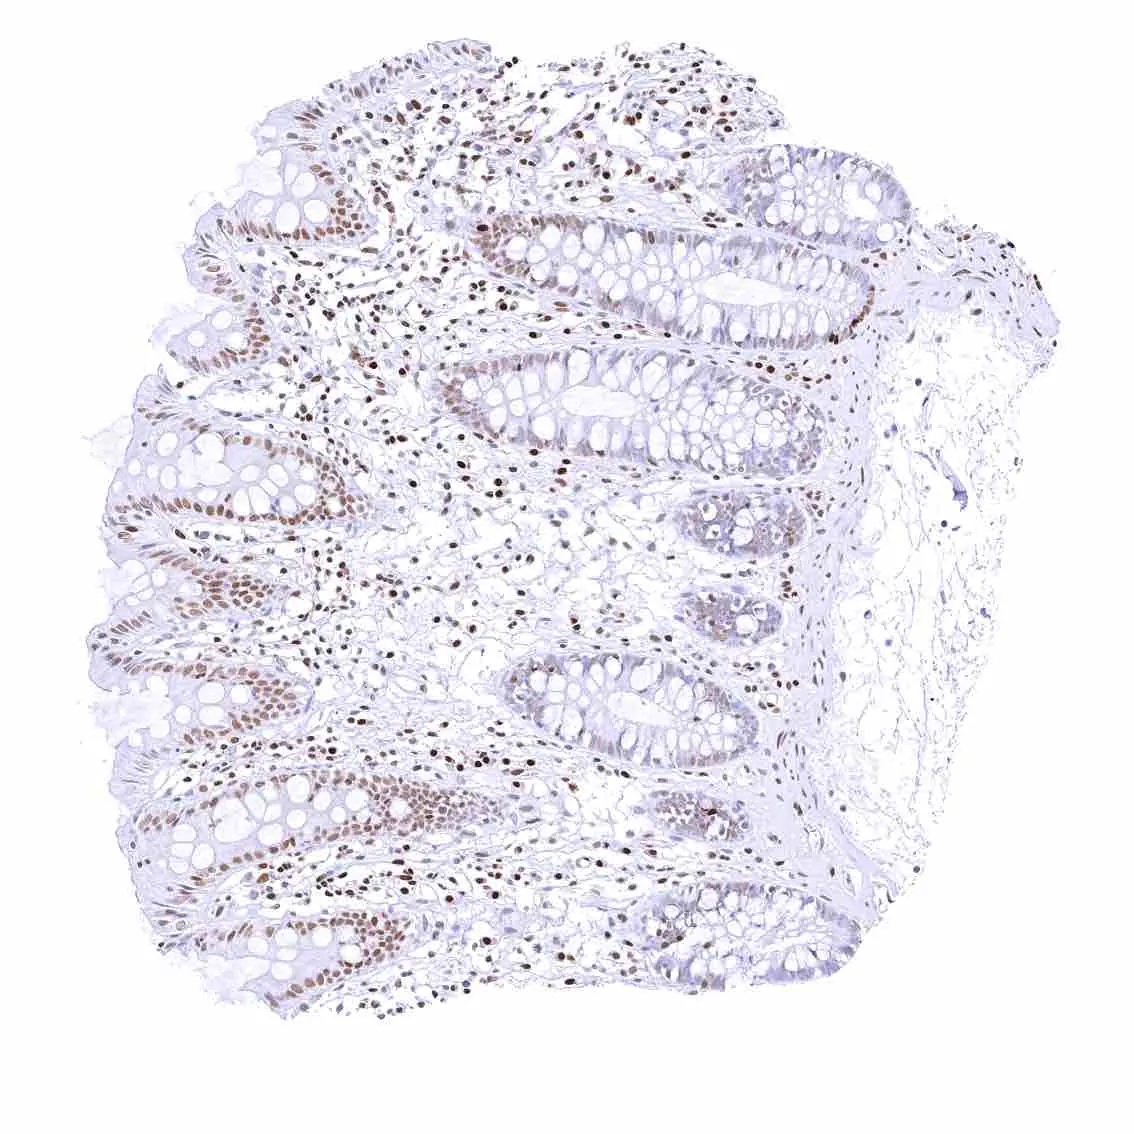

Colon descendens, mucosa